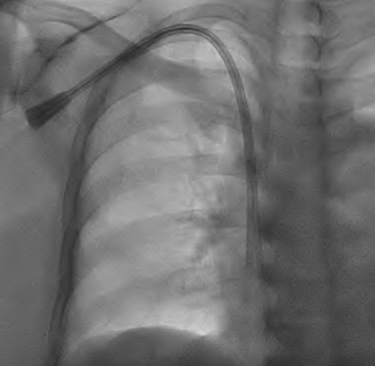

🚑 Tunnelled Dialysis Catheter Placement

Sometimes, patients need immediate dialysis access — especially when kidney failure develops suddenly or when a fistula is not yet ready for use.

In such cases, Interventional Radiologists place a tunnelled dialysis catheter into a large central vein. The catheter is tunnelled beneath the skin before entering the vein, reducing infection risk and allowing repeated dialysis sessions.

This procedure, performed with ultrasound and fluoroscopic guidance, ensures precise and safe placement, giving patients urgent access when they need it most.